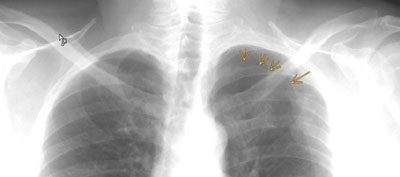

Zu sehen ist eine frische Rippenserienfraktur der 3. bis 5. Rippe links dorsal sowie ein Spitzenpneumothorax links apikal (die Pfeile markieren die Pleura visceralis der zusammengefallenen Lunge).

Beim Spitzenpneumothorax ist nur wenig Luft in den Pleuraraum geflossen. Da diese meist nach oben steigt, sammelt sie sich über der Lunge an. Im Röntgenbild sieht man dann die Luftansammlung über der Lungenspitze, daher der Name "Spitzenpenumothorax". Ein Spitzenpneumothorax wird meistens im Röntgenbild bemerkt und macht wie auch in diesem Fall selten Beschwerden im Sinne einer Dyspnoe.